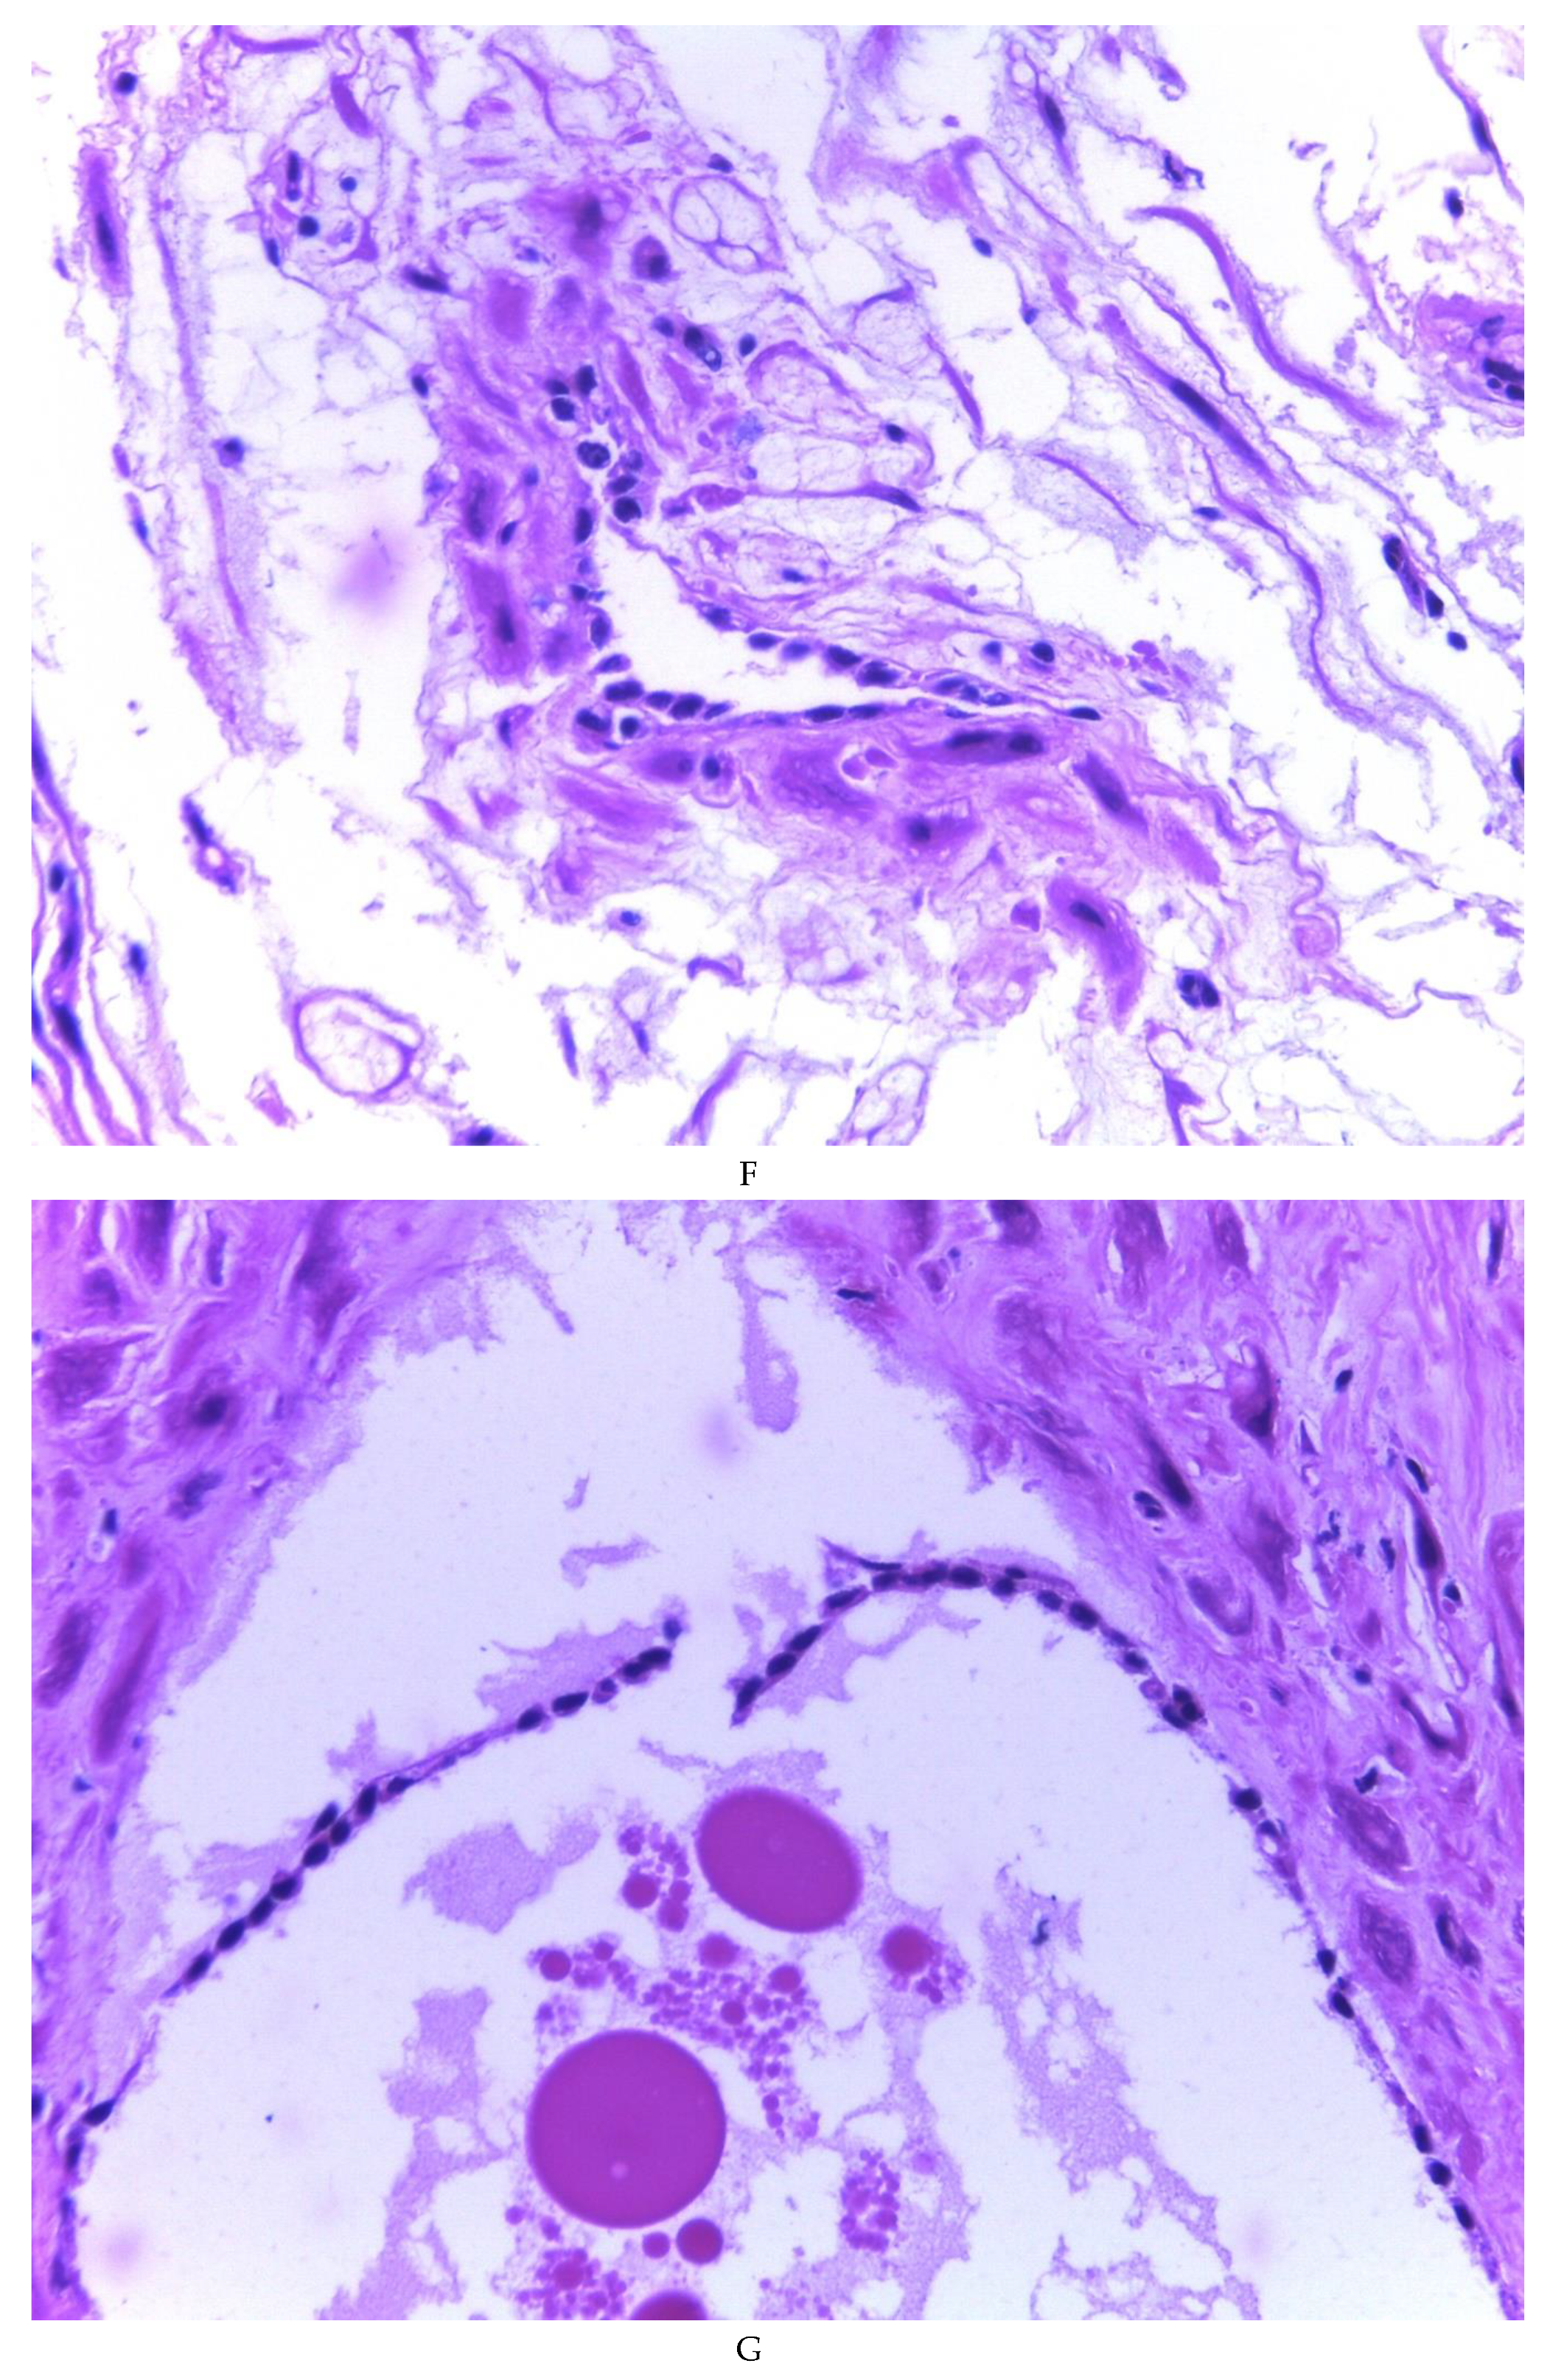

776 cases of endometriosis were collected between the two institutions participating in the study, in different anatomical sites (Table 1, Figure 1), in which 54 of them presented a myxoid stroma greater than 50% with respect to the cellularity of the samples. and that represent 6.95% of the total endometriosis examined with the following locations: omentum (4/20), ileum (2/4), ovary (14/216), parametria (2/9), soft tissues (28/235), salpingus (3/77), bladder (1/4). The clinical records of these patients were consulted and the common denominator was that the women were in the surgical (41/57) or physiological (7/39) puerperium in a period of time from 24 hours postpartum to six months after said event. Macroscopically, two different lesions were observed: the first one, which is the most frequent, presents as a non-encapsulated lesion with pushing edges of a fibromyxoid appearance; the second and less frequent, a well-defined lesion, partially or totally encapsulated, the cut surface is shiny, gelatinous in appearance, multilobed, light brown to brown in color with focal areas of recent and old hemorrhage, these lobes are separated by fibrous septa (Figure 2). Histologically, it was found in all the samples evaluated at least 50% of myxoid stroma with some fine connective tissue septa with proliferation of stromal cells (Figure 3A), which present four variants in their shape: (1) Epithelioid stromal cells of wide eosinophilic cytoplasm with round nucleus with small nucleolus (Figure 3B), (2) Pseudolipoblast-type stromal cells with moderate cytoplasm, multivacuolated in their cytoplasm that can present eosinophils or be clear cytoplasm, with central nuclei of granular chromatin (Figure 3C), (3) “pseudosignet ring” stromal cells with nucleus and cytoplasm rejected to the periphery giving the aforementioned appearance (Figure 3D) and (4) immersed spindle cells with small nucleus and barely visible nucleolus (Figure 3E); Among these cells, the epithelial component is observed, which is forming tubules that vary in diameter, ranging from small tubules and large cystic dilations of the gland that presents a layer of low cubic to cylindrical epithelium, generally with an atrophic appearance (Figure 3F). Hyaline globules were found in the glandular lumens (Figure 3G). The extracellular matrix showed a composition by glusocaminoglycans evidenced in 100% of the cases by staining present for AA (Figure 4A–C), but without staining for PAS; however, the latter stained on proteinaceous globular material in the lumen of the endometrial glands (Figure 4D). Immunohistochemistry for CD10 was positive in 100% of the stromal cells with a mild to moderate reaction in the cytoplasm and membrane with a decidual appearance (Figure 5A,B). The ER and PR showed nuclear expression in 100% of the cases, with greater intensity in the ER (Figure 5C) than in the RP (Figure 5D); both hormone receptors were expressed on endometrial epithelial cells as well as on stromal cells. The cases of myxoid endometriosis examined did not present cytological atypia suggesting any precursor lesion of epithelial or stromal origin.

Figure 3. Histologic features of myxoid endometriosis: A) Myxoid stroma in 50% or more of the tissue, with proliferation of stromal cells. Identified stromal cell variants: B) epithelioid cells, C) lipoblast-like cells, D) signet-ring-like cells, E) spindle cells. F, G, H) Epithelial component formed by glands of variable size, with simple cuboidal to columnar epithelium with a non-atypical atrophic appearance, occasionally accompanied by luminal hyaline globules.